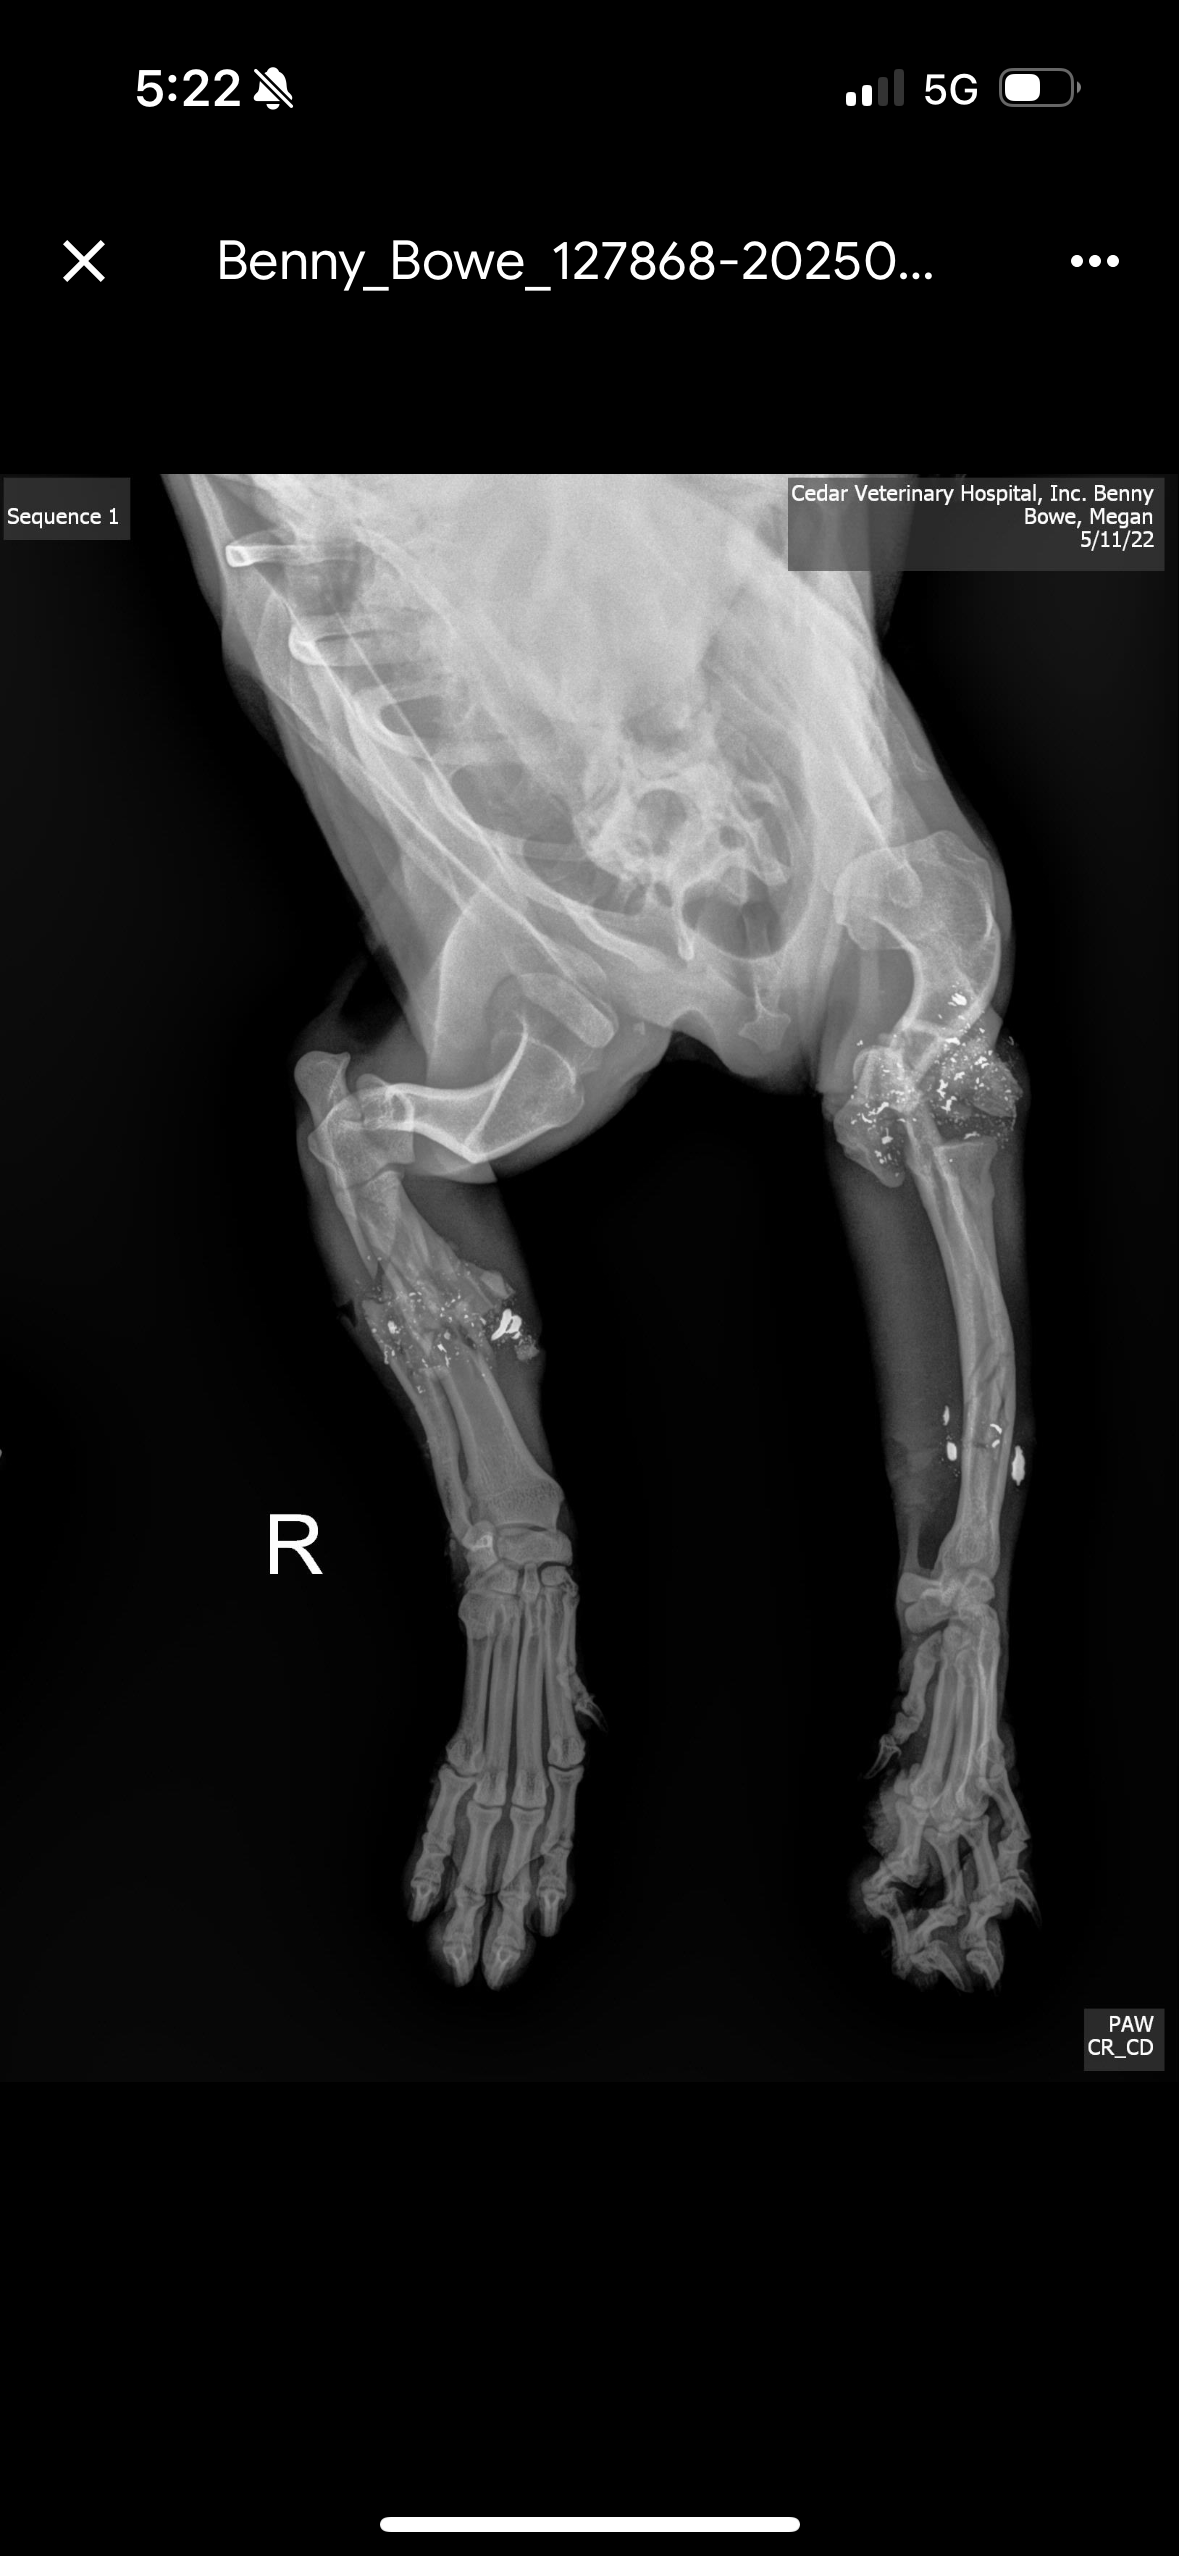

Benny was cruelly shot multiple times and left to die in an orchard south of Avenue 12 in late April. Both his front legs were broken, and his back foot was broken. He could no longer walk, but somehow he fought, crawled, and survived until help arrived. He was in excruciating pain, too weak to cry out or defend himself. Warning: The photos, x-rays, and videos are disturbing.

We rushed him to emergency care, where he was stabilized, treated for shock, and given fluids. He’s now receiving regular vet visits, bandage changes, and preparing for a critical procedure to remove bullet fragments and possibly insert pins to stabilize one of his legs. The other front leg may still require amputation if it doesn’t heal.